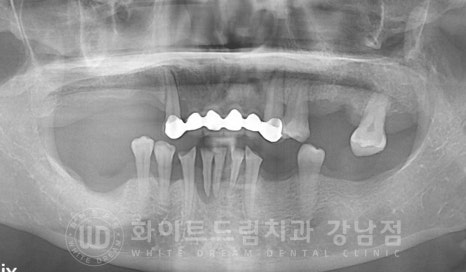

환자분 구내에 세팅된 최종 크라운입니다.

초기 계획에 따라 낮아진 수직 고경도 어금니 임플란트 보철을 세팅을 통해

정상 교합 높이를 회복한 것이 확인됩니다.^^

이후 임시 접착 상태로 1-2주간 환자분이 새롭게 생긴 치아를 사용해 보시면서

불편하신 점이 없는지 확인 & 적응하는 시간을 가지게 됩니다.

별다른 불편함이 없으실 경우는 이 보철을 최종 부착하며 치료를 종결하게 된답니다. ^^